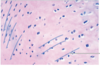

Cardiac Muscle

25

Identify:

Cerebral Cortex - Pyramidal Cells